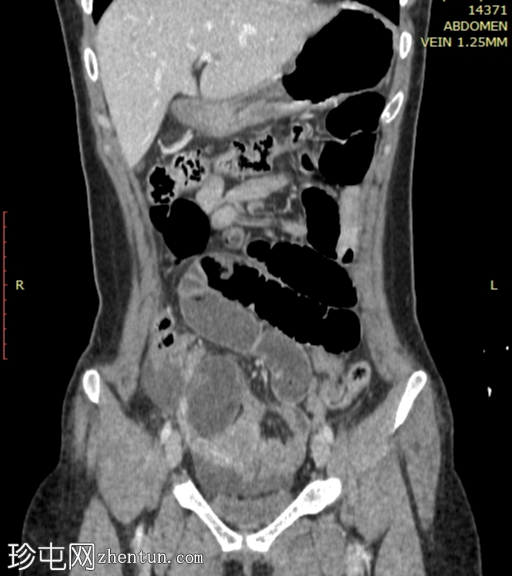

冠状位增强扫描(门静脉期)

小肠袢明显扩张,左侧附件区可见双移行点,远端回肠短段闭袢梗阻,肠颈位于左侧输卵管/左侧子宫血管附近。

肠系膜血管充血,腹盆腔可见游离液体,提示肠系膜充血。

远端回肠袢和结肠已减压。

无肠缺血或穿孔的影像学证据。